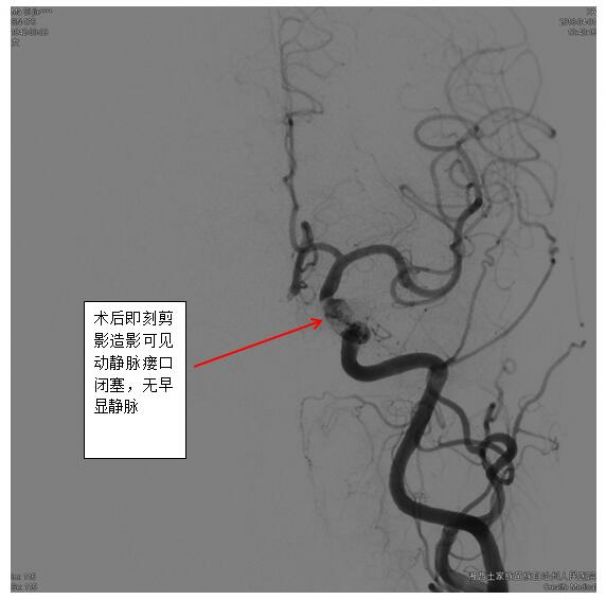

一旦怀疑DAVFs,神经内科一病区医生迅速和患者及家属沟通,及时完成脑血管造影,第一时间确诊患者为海绵窦区DAVFs(供血动脉为左侧颈内动脉海绵窦段,向左侧岩下窦及通过海绵间窦向对侧岩下窦引流)。

最终,经过充分准备,凭借精湛的技术,手术组田勇副主任医师、梁承财主治医师在刘凡教授指导下,在护理人员及麻醉师同力合作下,顺利通过颈内静脉-岩下窦入路,采用弹簧圈辅助加注入onxy胶的方式完全闭塞瘘口,患者术后没有神经功能缺损。